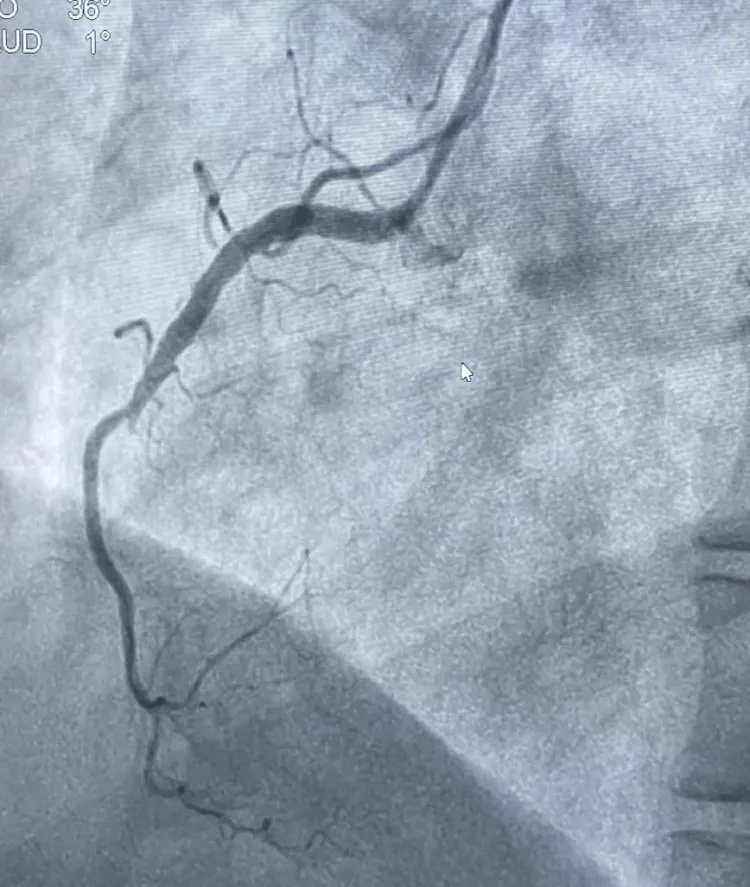

情况紧急,胸痛中心迅速响应,在与家属沟通并签署知情同意书的同时,同步办理住院手续,全程开通绿色通道,最快的速度把吕女士送入导管室接受急诊PCI治疗(经皮冠状动脉介入治疗)。在王宁夫主任医师指导下,徐鹏和钱宇峰副主任医师为她进行介入治疗,术中发现她的右侧冠状动脉近段完全闭塞,通过球囊扩张并植入支架,成功开通了堵塞的血管,恢复了心肌供血。

术前右冠中段完全闭塞